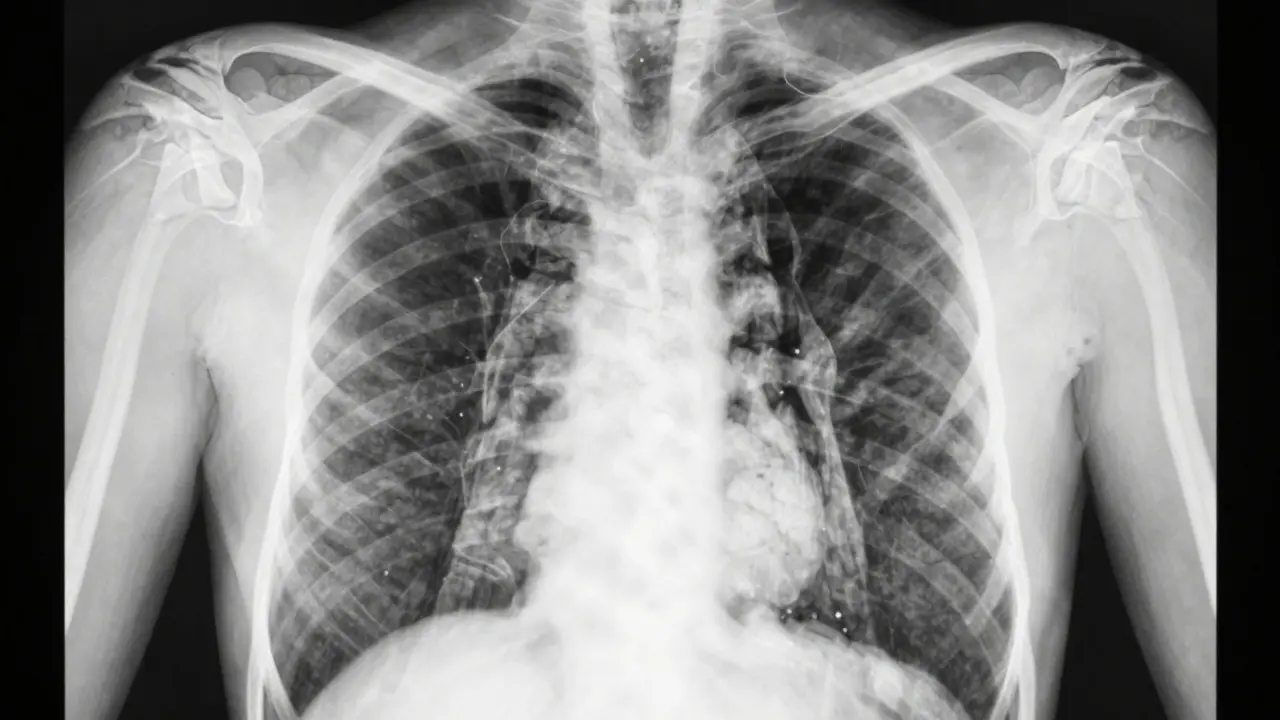

Na rentgenovém snímku plic nevidíte, že někdo vypírá THC. Žádná rentgenová technologie nezobrazuje přítomnost kapaliny, oleje nebo chemických látek ve vdechovaném paru. Rentgen ukazuje jen strukturu tkaní - kosti, plíce, srdce, cévy. Nevidíte, co tam dýcháte, jen jak to ovlivňuje tělo.

Rentgenový snímek je jako černobílá fotografie vnitřních struktur. Kosti jsou bílé, protože jsou husté a blokují záření. Plicní tkáň je šedá, protože je lehká a propouští více záření. Tekutiny, jako je krev nebo hlen, se na snímku objeví jako tmavší oblasti, ale jen pokud jsou dostatečně husté - například při zápalu plic nebo tekutině v plicích.

Vypírání THC nezanechává na rentgenu žádný charakteristický vzor. Neexistuje žádný „signál“ nebo „stopy“ od vape, které by lékař mohl jednoznačně identifikovat jako vypírání. To znamená, že i kdyby někdo vypíral denně, jeho rentgen může vypadat naprosto normálně - až do chvíle, kdy se objeví poškození plic.

Tyto změny už na rentgenu vidět můžete. Plicní tkáň se může objevit jako „mramorová“ nebo „zmatená“, což naznačuje zánět nebo jizvy. V některých případech se objeví plynové vakúny nebo kolem plic tekutina. Ale to už je pozdní fáze - ne vypírání samo o sobě, ale jeho následky.

Porovnání zdravých a poškozených plic s příznaky EVALI.